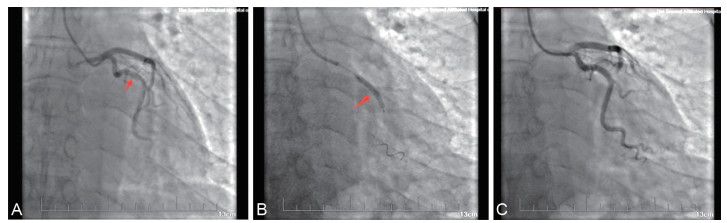

突发性耳聋合并非ST段抬高型心肌梗死1例

刘阳, 冯勇军, 刘千涵, 邓宇元

2026, 24(1): 171-174. doi: 10.16766/j.cnki.issn.1674-4152.004355

87 6

摘要:

本文报道1例以突发性感音神经性耳聋为首诊断入院的患者,在治疗过程中出现胸闷不适,后诊断为急性非ST段抬高型心肌梗死。尽管突发性感音神经性听力损失(sudden sensorineural hearing loss,SSNHL)的病因尚不清楚,目前认为可能的机制包括病毒感染、内耳微循环障碍、免疫因素、膜迷路积水等,但越来越多的证据表明其潜在的心血管病理机制。近期相关研究揭示了急性心肌梗死(acute myocardial infarction,AMI)和SSNHL之间的关联,本病例的结果进一步支持了SSNHL发展中潜在的血管病理机制,并强调了临床医生处理SSNHL患者时需要警惕AMI的发生和发展。